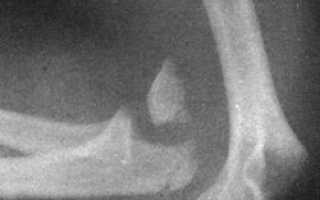

Диагностика вывиха предплечья

В анамнезе — травма. Сустав отёчен и деформирован. На задней поверхности, на расстоянии от плеча, под кожей выступает локтевой отросток. Нарушены треугольник и линия Гютера. Предплечье укорочено. Активные и пассивные движения в локтевом суставе отсутствуют, их попытка вызывает острую боль. Отмечается положительный симптом пружинящего сопротивления.

Лабораторные и инструментальные исследования

На рентгенограммах в двух проекциях видно разобщение сочленяющихся поверхностей плеча и предплечья.